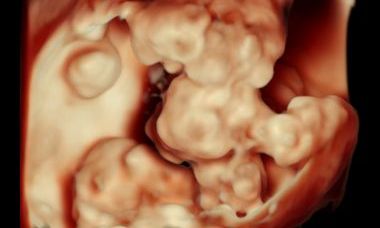

The January issue of Ultrasound in Obstetrics & Gynecology includes a meta-analysis evaluating the use of transvaginal ultrasound for diagnosing parametrial involvement in deep pelvic endometriosis, a retrospective study comparing the use of intertwin estimated fetal weight discordance vs singleton and twin fetal growth charts for predicting adverse perinatal outcomes in twins, a paper assessing the effectiveness of the first-trimester anomaly scan, and a prospective study examining the efficacy of a multimodal sonographic approach compared with transvaginal ultrasound for endometrial assessment in abnormal uterine bleeding.